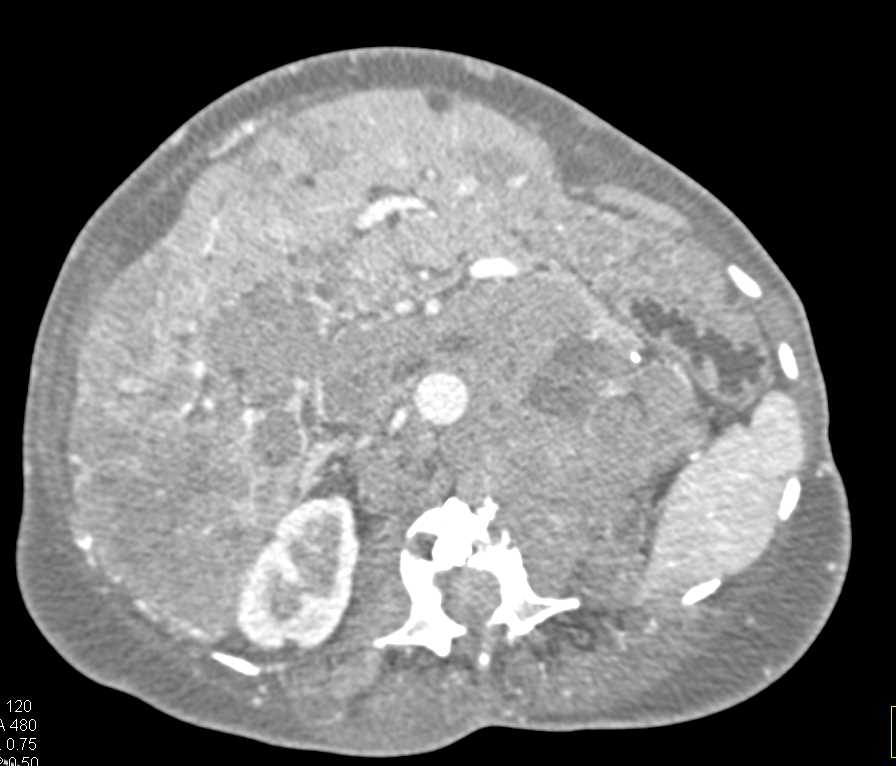

Multiple Myeloma